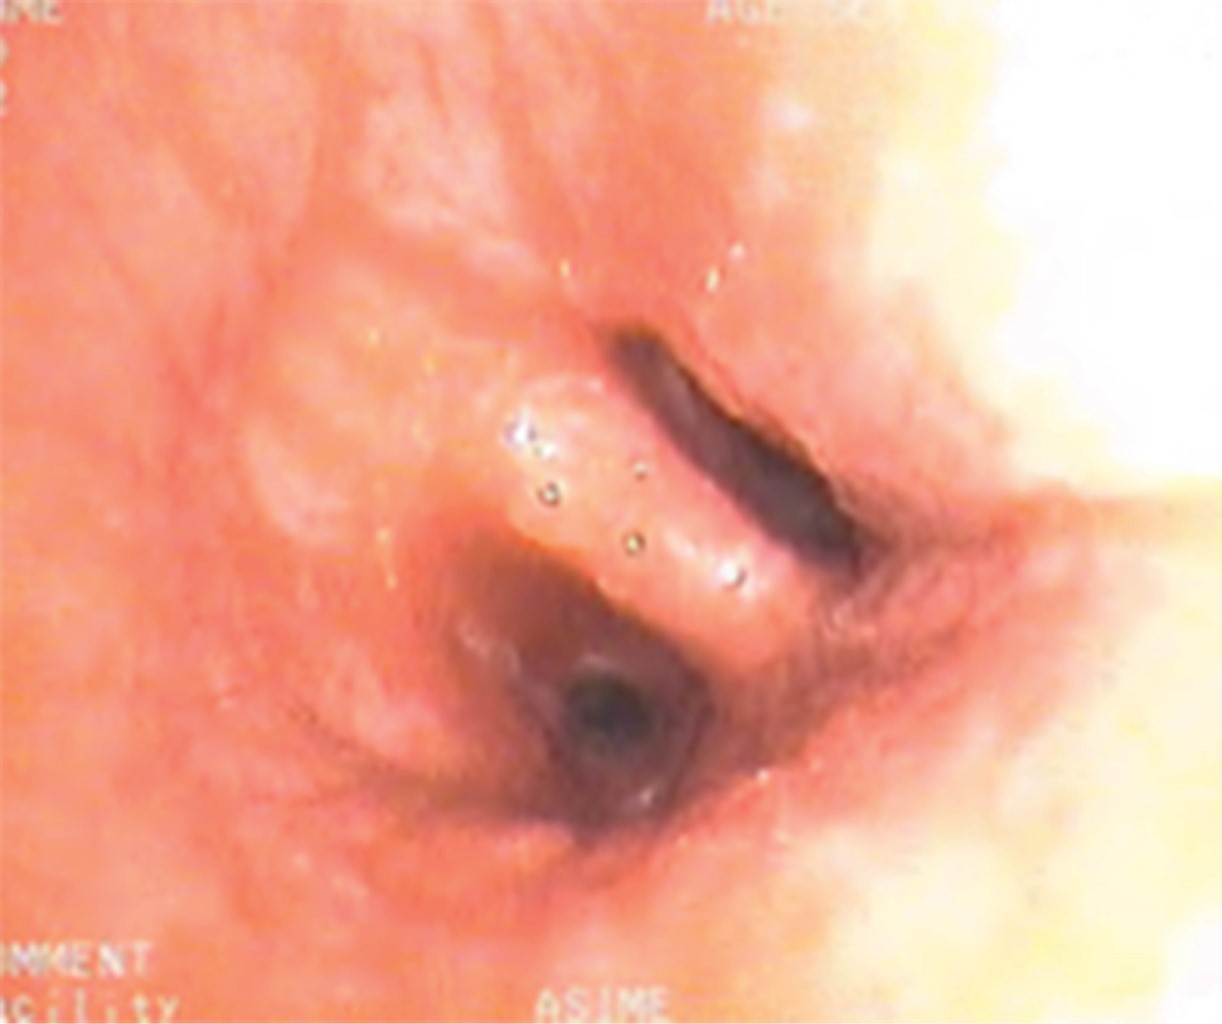

Hemoptisis grave como forma de debut de una estenosis de venas pulmonares izquierdas

La fibrilación auricular es la arritmia más común. Es una patología que conlleva un alto coste sanitario y perjudica la calidad de vida de los pacientes. La ablación percutánea de las venas pulmonares es una terapia consolidada para su tratamiento y varios estudios han demostrado que la recidiva a largo plazo y la mortalidad es menor en comparación con pacientes tratados con medicación antiarrítmica. Presentamos el caso de un varón de 48 años, no fumador, con antecedente de taquicardia auricular incesante de difícil control que acude a urgencias por hemoptisis. El cuadro clínico se debió a una oclusión completa del segmento distal de las venas pulmonares izquierdas como complicación de una ablación percutánea previa. La estenosis de la vena pulmonar es una complicación poco común de la ablación para tratar la fibrilación auricular, siendo un diagnóstico precoz fundamental para mejorar el pronóstico.

Figura 2